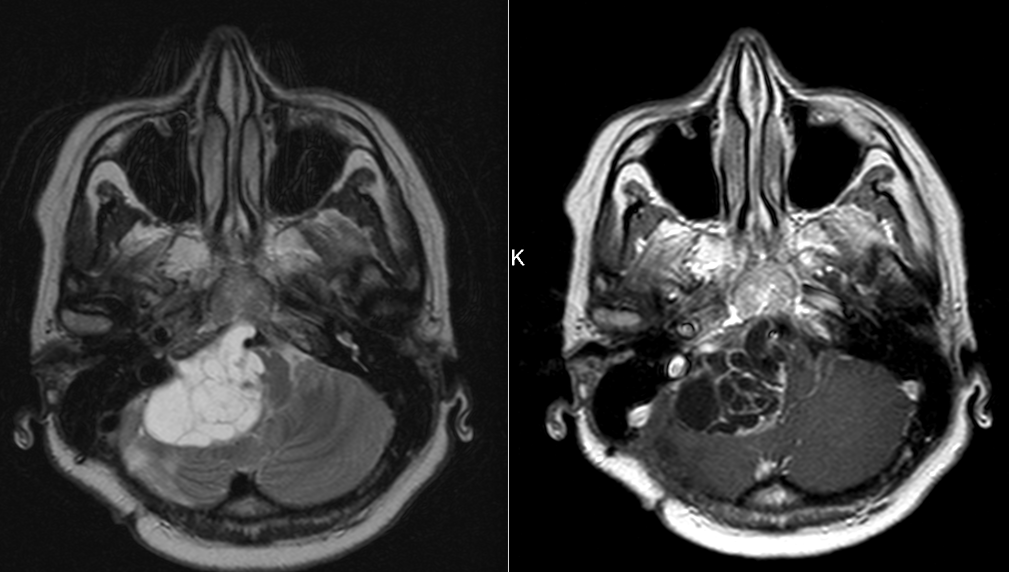

RMN cerebral cu substanță de contrast – Este cea mai precisă metodă pentru diagnostic. RMN-ul evidențiază tumora și arată dimensiunea și localizarea exactă precum și eventualele complicații (hidrocefalie). Pentru tumorile de mici dimensiuni există o secvență specială care vizualizează mai bine nervii cranieni (în funcție de tipul de aparat se poate numi CISS, TRUFI sau FIESTA).

Pe RMN, schwanomul vestibular apare ca o masă nodulară cu priză de contrast, bine delimitată, localizată în spațiul dintre stânca temporală și cerebel, cu origine în porul acustic intern.

Abordul retrosigmoidian – preferat de neurochirurgi, este cel mai folosit. Oferă posibilitatea de a păstra auzul (deși nu poate oferi garanții). Poate fi folosit pentru orice tip de schwanom vestibular dar este util în special pentru tumorile de dimensiuni medii și mari, cu dezvoltare în cisterna ponto-cerebeloasă sau cu compresiune pe trunchiul cerebral.

Abordul fosa mijlocie – foarte rar folosit, luat în considerare în trecut pentru tumori mici, cu conservarea auzului. Rezecția unui schwanom vestibular este de cele mai multe ori o intervenție de durată, laborioasă și care trebuie efectuată de un neurochirurg experimentat. Riscurile includ pierderea auzului, afectarea nervului facial (pareză facială) sau a altor nervi cranieni (cea mai invalidantă fiind afectarea nervilor vag și gloso-faringian, cu tulburări de deglutiție). Pentru minimizarea acestor riscuri se utilizează metode de monitorizare electrofiziologică a acestor nervi, cu rezultate bune însă doar pentru nervul facial. Cu toate acestea, mai ales în cazul tumorilor de mari dimensiuni, este de așteptat un grad de pareză facială imediat postoperator, care se va recupera ulterior.